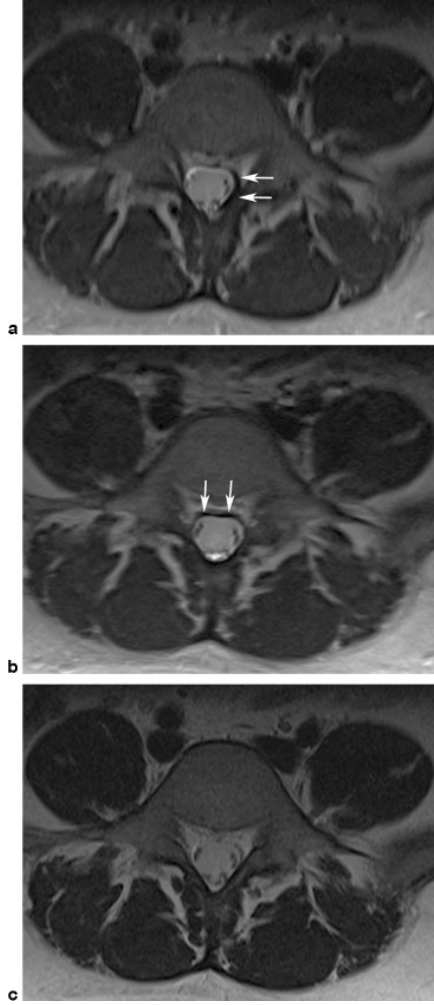

截断伪影常见于 MR 信号强度突然变化的组织界面,如脂肪-肌肉和脊髓-脑脊液界面,可能导致脊髓内出现虚假高信号,易被误解为脊髓空洞或损伤。通过校正编码方向等方法可改善。